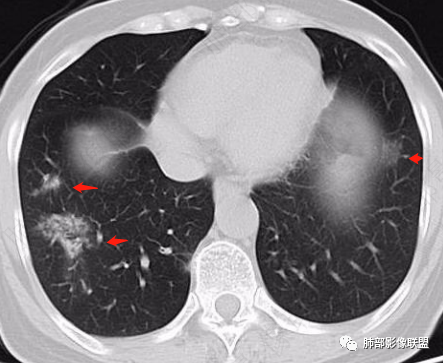

2、CT表现为两肺下叶结节影、斑片影、磨玻璃影,沿支气管血管束分布,部分支气管壁显示增厚。粗略一看部分病灶内似可见“细网格影”,但是仔细观察,可发现此“细网格影”不同于我们常见的“细网格影”,尤其是右肺下叶病灶,可以观察到病灶内部的网格上有高密度结节感或颗粒感,部分层面见“反晕征”,且反晕的边缘亦可观察到结节感。未见胸腔积液。

2、好发部位与其它结核类似,上叶及下叶背段为主。 3、烟花征,反晕征,环呈结节状,可以伴随空洞,树芽征,结节灶,胸水。(反晕征:一般周围实性环形高密度影,中央呈低密度;一般环超过圆的3/4,结核的环主要是小叶核心结节组成,类似于多发树芽征聚集,边缘结节感。中央的晕:可以是腺泡结节,树芽征,细网状,磨玻璃影,很少正常,主要成分是小叶内间质增厚、小叶核心结节、肺泡内病变。)其实也体现了结核的多灶性、多态性特点。